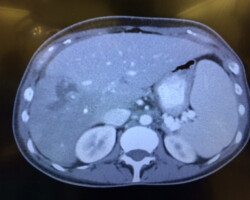

Resection of large retroperitoneal sarcoma including right and transverse colectomy and right hepatectomy